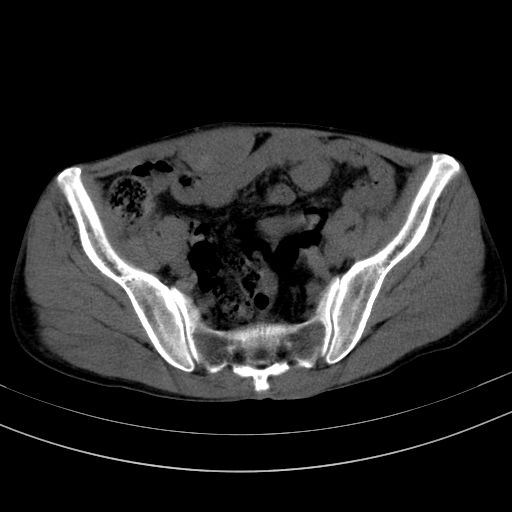

以下是引用37度在2010-1-9 14:37:00的发言:[br]1.双肾囊肿,左肾积水结石,.胆总管轻度扩张;[br]2.病灶在腹膜外,考虑纤维瘤。

以下是引用dyqct在2010-1-9 17:56:00的发言:[br]考虑:1.双肾囊肿,左肾积水结石、旋转不良。[br] 2.右侧腹直肌血肿或纤维瘤。[br]肠道准备不好。做个增强。